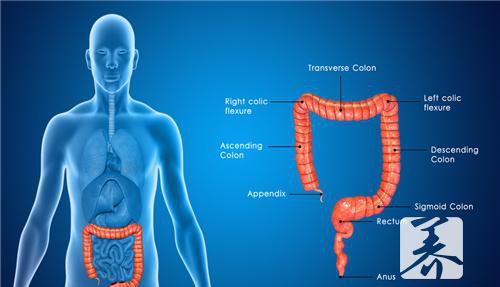

直肠

男人一般进食脂肪和蛋白质类食物比女人多,而科学研究表明,食用过多的脂肪和蛋白质是发生直肠癌的一个重要原因。因此为了防止患直肠方面的疾病,餐桌上要经常有富含纤维素的蔬菜水果等食品。